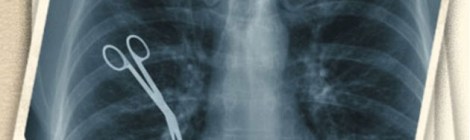

México, el país de las negligencias

En este país es normal escuchar aterradoras historias de personas que ingresaron a un hospital con un dolor en el estómago, y salieron con un pulmón perforado, con amputaciones o […]